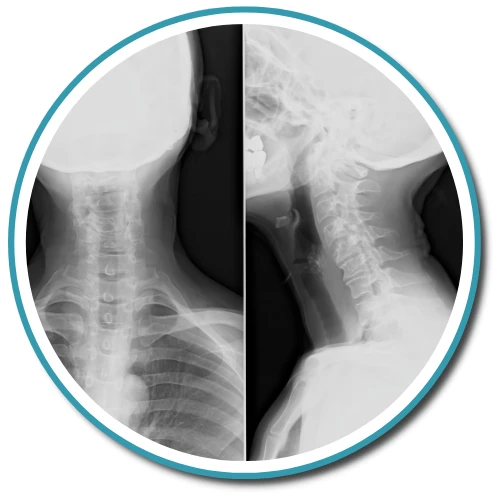

A Chiropractor in Summerville can provide a range of services to help you feel your best. Whether you are experiencing musculoskeletal pain, playing sports and need a chiropractor, or just looking to improve your overall health and vitality, our friendly chiropractic team at McIntyre Family Chiropractic is here to help.

We offer a wide range of chiropractic therapies and pain management methods to address conditions such as low back pain or severe back issues. Our clinic in Summerville focuses on determining the root cause of your discomfort and using natural healing techniques to achieve your wellness goals. Our team is dedicated to answering all your questions and assisting you in harnessing your nerve system's natural ability to heal.